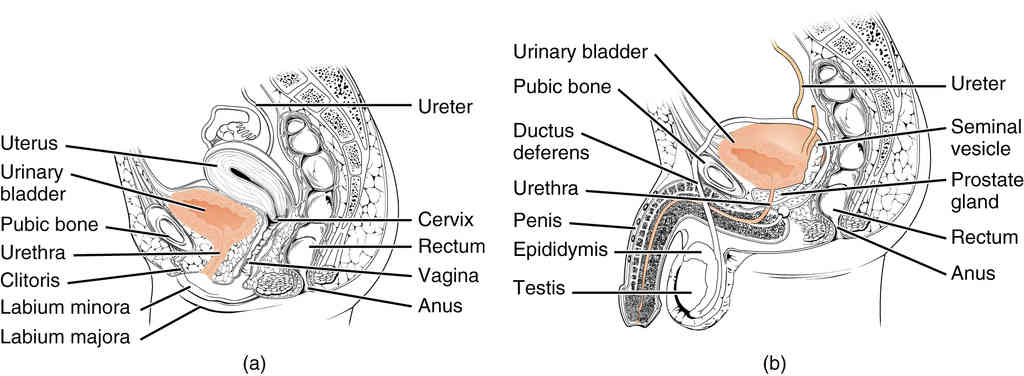

This page is under construction. For now, it is just a resource of the images found in the OpenStax Anatomy and Physiology Handbook. It wil slowly change into a revision tool. Each slide has a number. Use this to refer to the slide. When completed, it will have an unlabelled section, with labelled slides in parallel. On the unlabelled slides, write your answer and use the labelled slide to assess yourself. Keep track by also noting the number on each slide. Improvement at each attempt is important, more so than full marks on a first attempt.